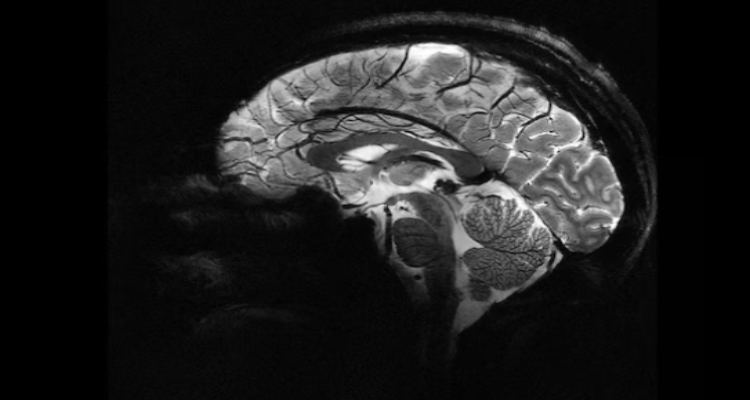

Researchers from the Institute of Science and Technology Austria (ISTA) and the Medical University of Vienna have made important discoveries about the hippocampal CA3 region of the brain, which plays a vital role in memory storage. Their study, published in *Cell*, reveals that the human brain has distinct features compared to animal models, especially rodents.

Unlike in rodents, the neural connectivity in the human CA3 region is sparser. Previous studies largely focused on animals, leaving gaps in our understanding of human-specific brain functions. To fill this gap, the researchers studied brain tissue from epilepsy patients who underwent neurosurgery, allowing them to examine intact human hippocampal samples.